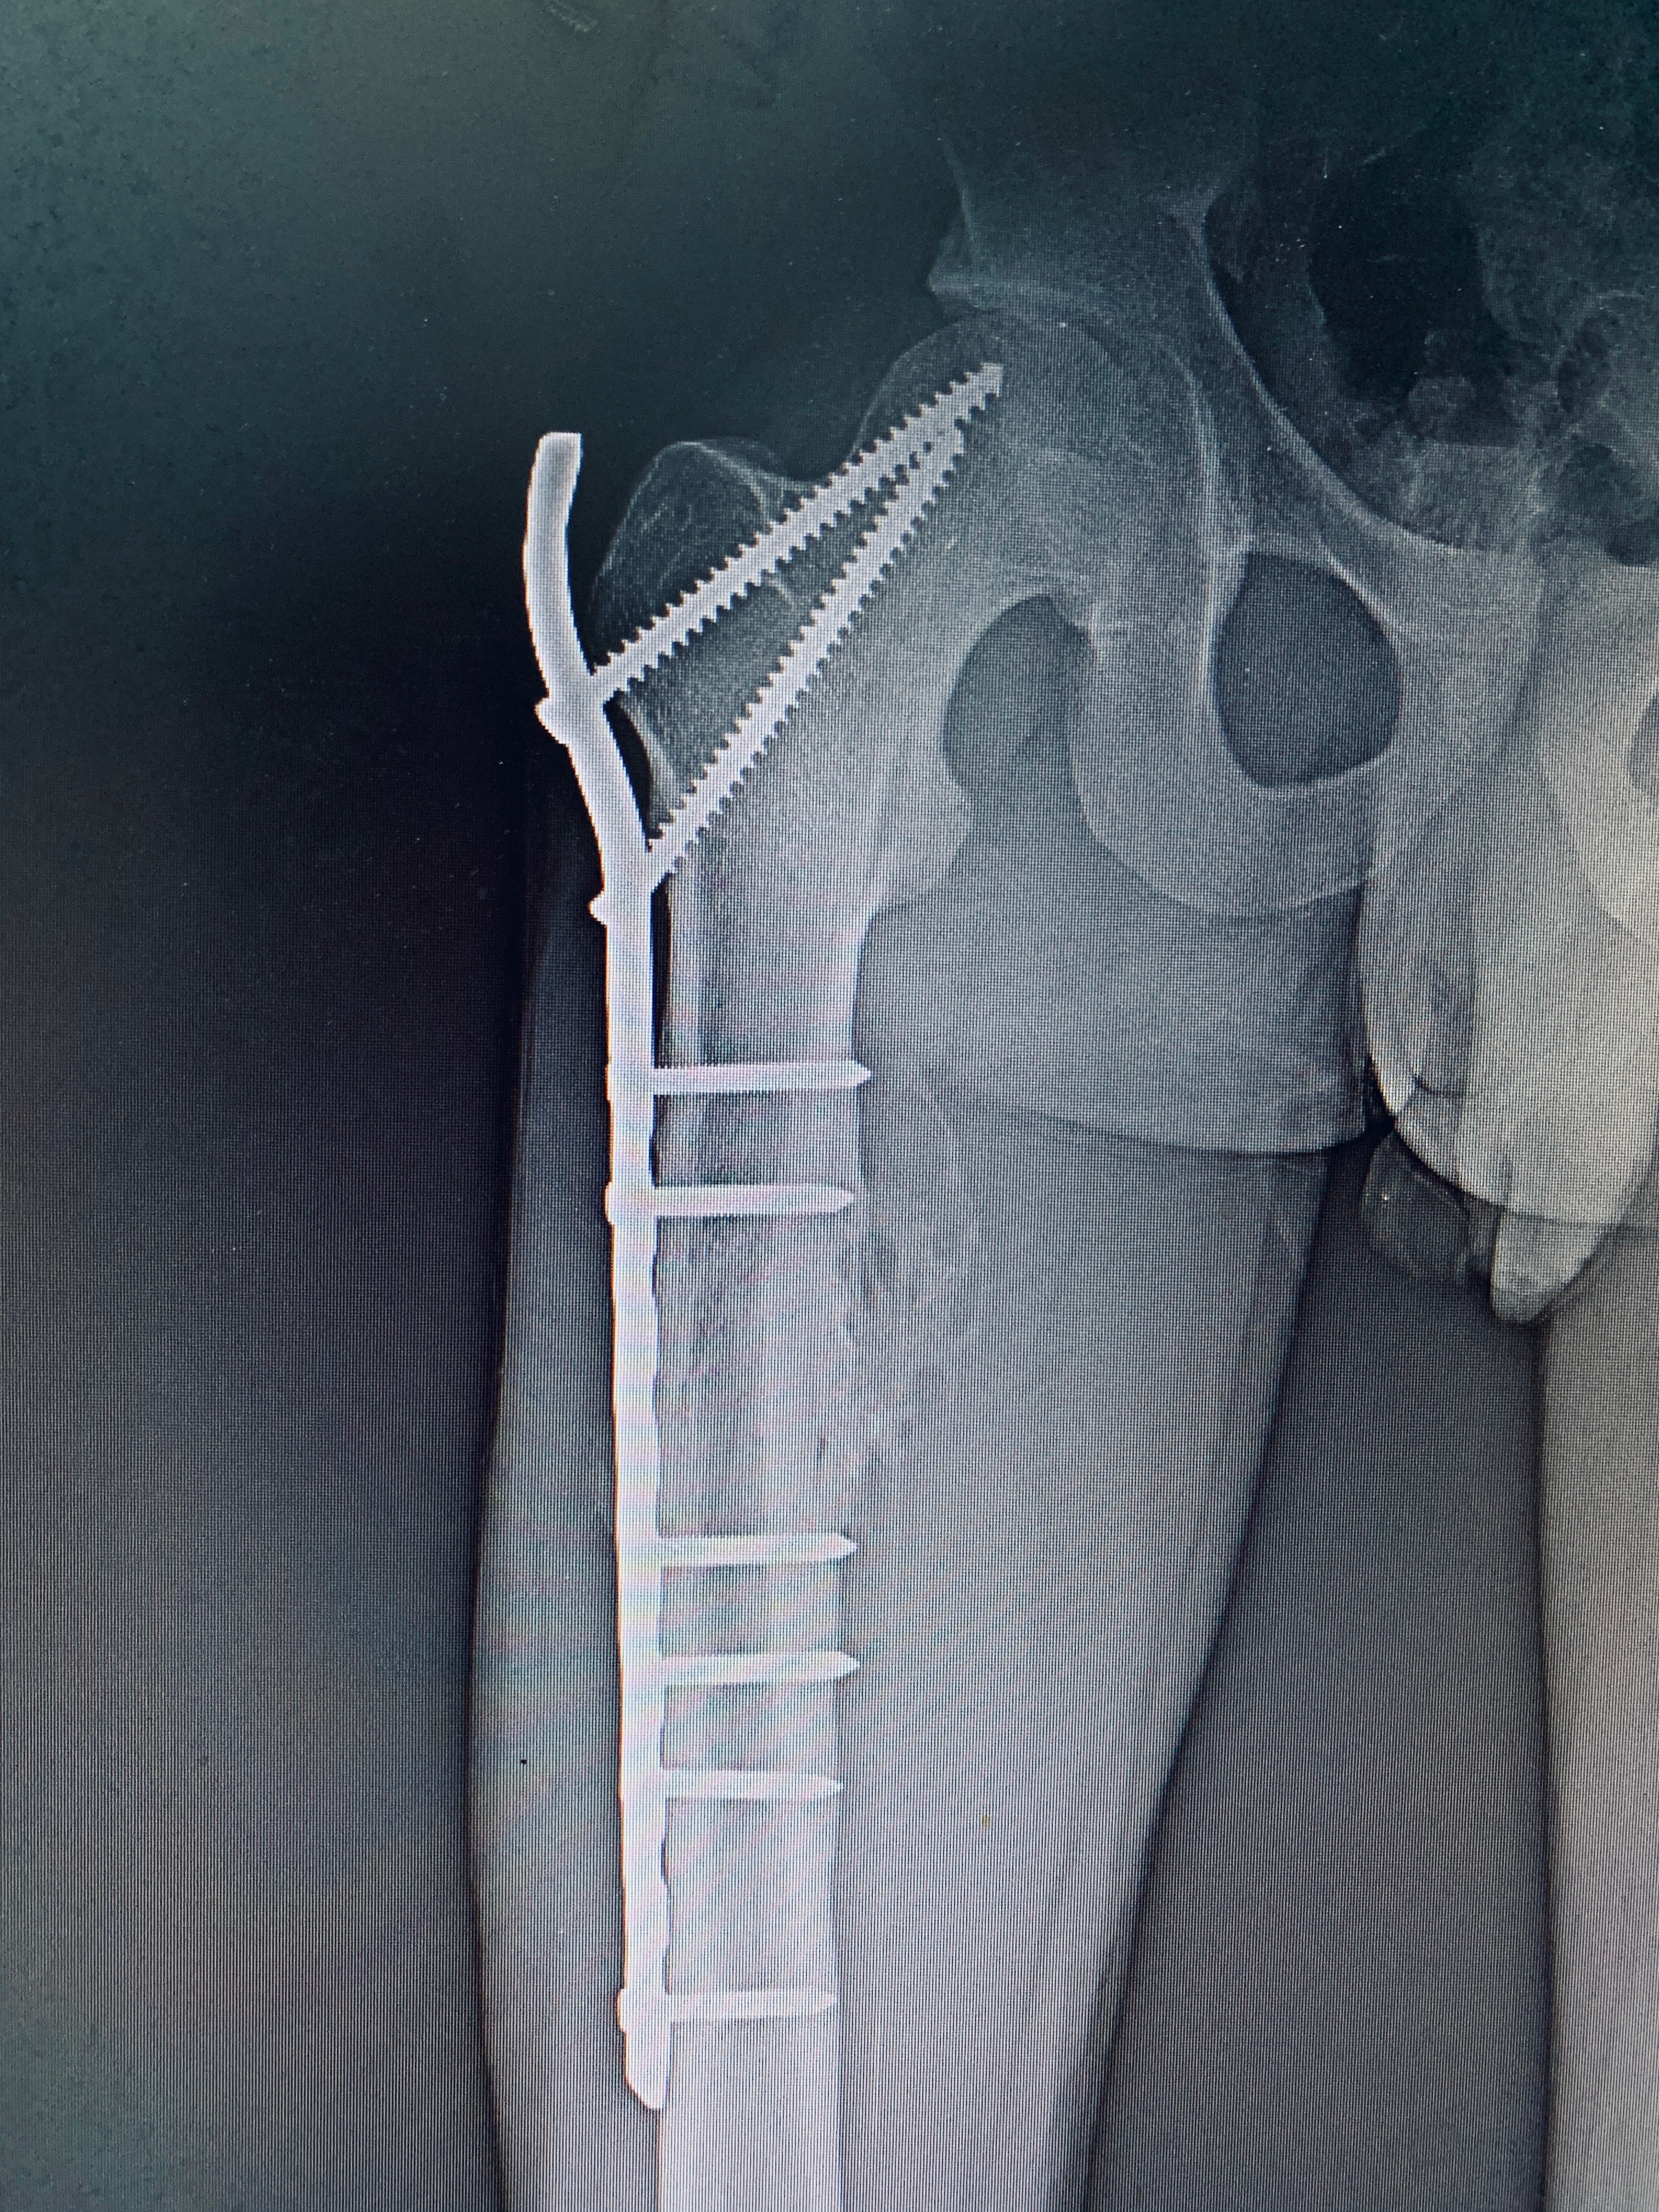

ORIF WITH PFLCP

A 21 year old male case of post-traumatic right-sided subtrochanteric femur fracture was treated.

Surgery performed was open reduction & internal fixation with Proximal Femoral Locking Compression Plate.